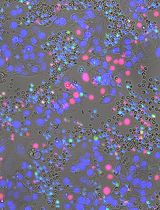

Macrophages maintain tissue homoeostasis by regulating inflammation and tissue repair mechanisms. Thus, the fate of macrophages has an impact on the state of the tissue. The aim of this protocol is to quantify macrophage survival using high content microscopy and image processing software. Here, we describe a high-content image based protocol to assess the effect of diverse stimuli in combination with pharmacological treatments on macrophage survival in a quantitative, unbiased and high-throughput manner.

Macrophages are phagocytic innate immune cells and are the main drivers of inflammation in tissue (Medzhitov, 2008). These cells are associated with cancer together with autoimmune, autoinflammatory, infectious, neurodegenerative and metabolic diseases (Ginhoux and Jung, 2014). In this context, the role of macrophages in inflammation is well-studied, however, the impact of macrophage survival in non-infectious and infectious diseases is largely unknown. Our study showed that the activation of certain pathogen-associated receptors (PRRs) can induce macrophage survival (Eren et al., 2016). We described a molecular mechanism that demonstrated how an obligate intracellular pathogen exploits PRR-induced cell survival (Eren et al., 2016). Thus, further studies are necessary to understand the role of macrophage survival in different disease settings.